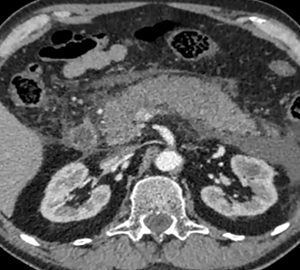

Pte femenino de 52 años, Mc: dolor abdominal difuso, App: hta, Mh: Losartan, A qx: osteosíntesis lumbar.